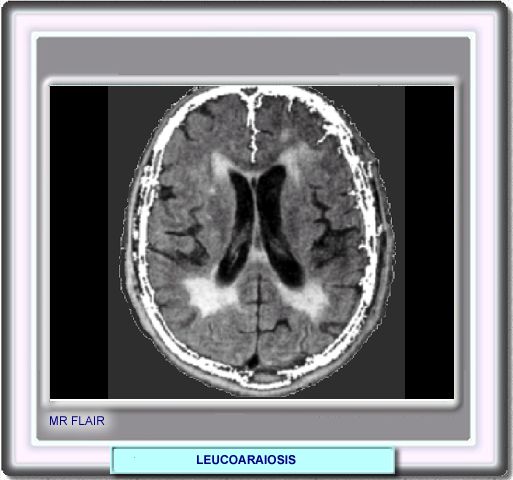

LEUCOARAIOSIS

Mientras que en la TC la leucoaraisosis se muestra como una hipodensidad localizada en la sustancia blanca periventricular y de los centros semiovales, en la RM en secuencias de densidad protónica, T2 y FLAIR (fluid-attenuated inversion recovery) se muestra como lesiones hiperintensas

Ver imagen en RM FLAIR